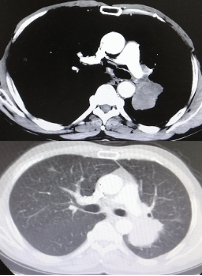

影像学-增强CT检查:右肺上叶中心型肺癌伴阻塞性肺炎,左肺下叶占位性病变,长径:2.9cm;纵隔及双肺门淋巴结转移,较大位于7组,短径1.1cm,肝脏多发点状异常密度影,考虑转移,多发骨转移。

CT检查——基线

影像学-增强CT检查:左肺见不规则软组织影,包绕肺门结构,病变轴位长径约7.5cm,左肺散在结节影,最大约4.5cm;纵隔、肺门见多发淋巴结肿大,纵隔7组短径约2.0cm。